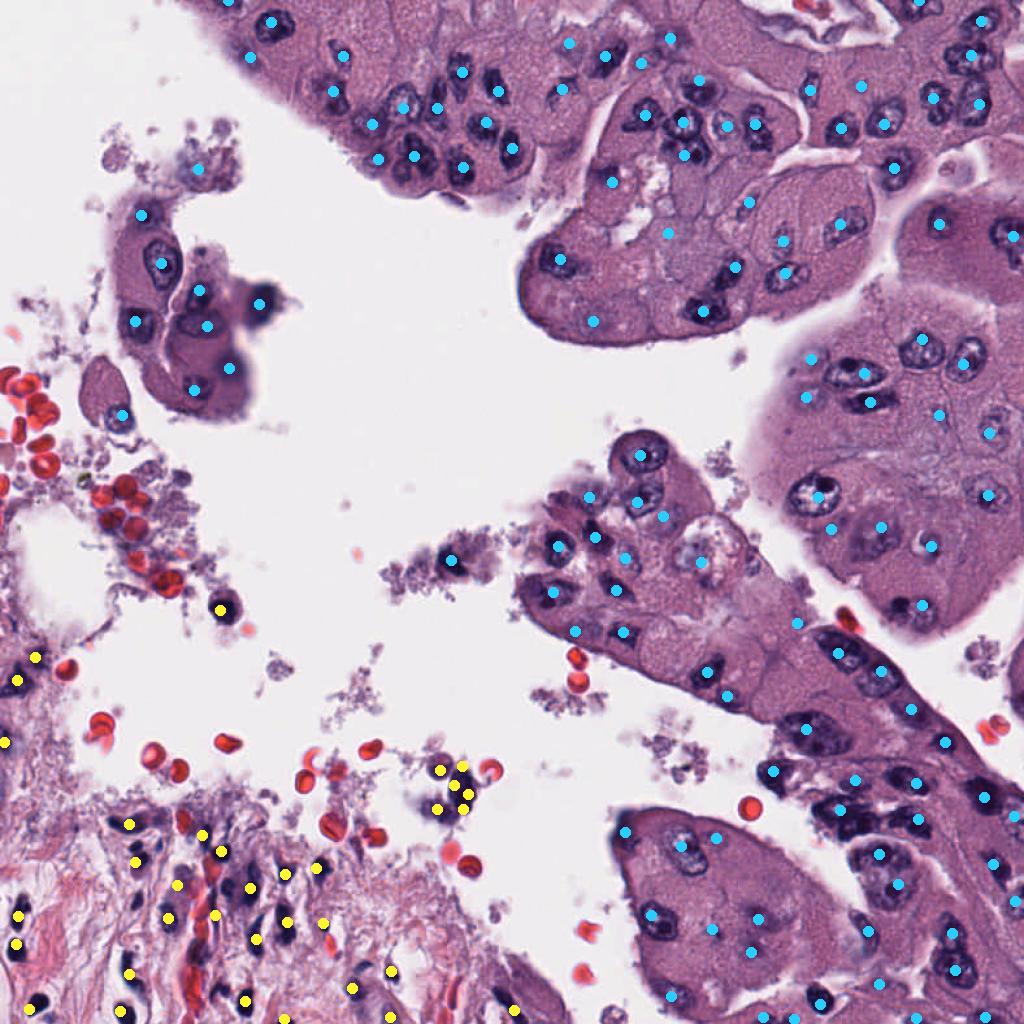

Appendix 0.A Segmentation ground truth generation with NuClick

We utilize NuClick [1], a pretrained nucleus, cell and gland segmentation model444Publicly available at https://github.com/navidstuv/NuClick, last accessed 24.11.2023, to extend the cell annotations from centroid coordinates to segmentation maps, as visualized in Figure 5. It relies on a guiding signal, in our case the cell point annotations, together with the input image for instance segmentation. Pretrained weights are only available for nuclei segmentation555https://drive.google.com/file/d/1MGjZs_-2Xo1W9NZqbq_5XLP-VbIo-ltA/view, last accessed: 24.11.2023, for this reason we extend the ground truth to a nuclei segmentation mask instead of a cell segmentation mask.

Appendix 0.C Ablation study: Different values for soft IS ground truth

The value for soft IS was originally chosen based on a visual review. To investigate, whether there would be a more suitable value, we conducted an ablation study with , analyzing the performance of the soft IS model. Figure 7 shows an example of the soft IS mask for all considered values. The internal train and validation set were used for training and evaluation. The highest mean F1-Score is achieved for , while our initial choice shows a slightly lower performance by -0.6%. Notably, the choice of appears to be a compromise between precision and recall (Table 5). While lower lead to a more precise cell detection, this comes at the cost of a higher number of missed cells (false negatives). The opposite is the case for larger values. Overall, while the difference in F1-Score for and is minor, utilizing for future work is recommended.